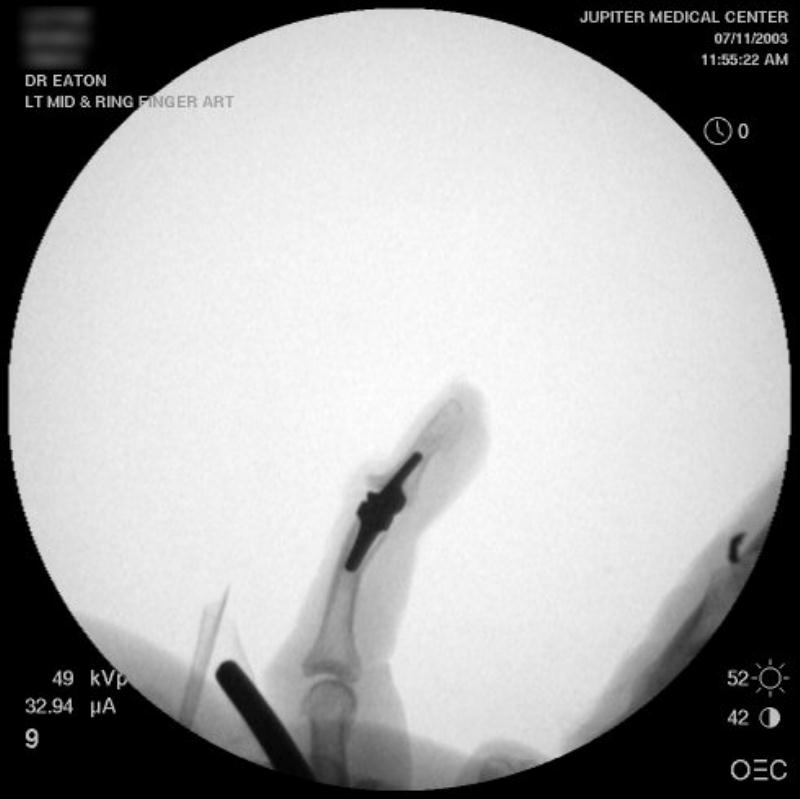

Intraoperative fluoroscopy using the same technique as above. The trial spacers:

The final implant:

Xrays one year out.